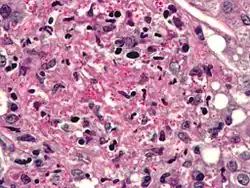

Histoplasma

Histoplasma Darling, 1906